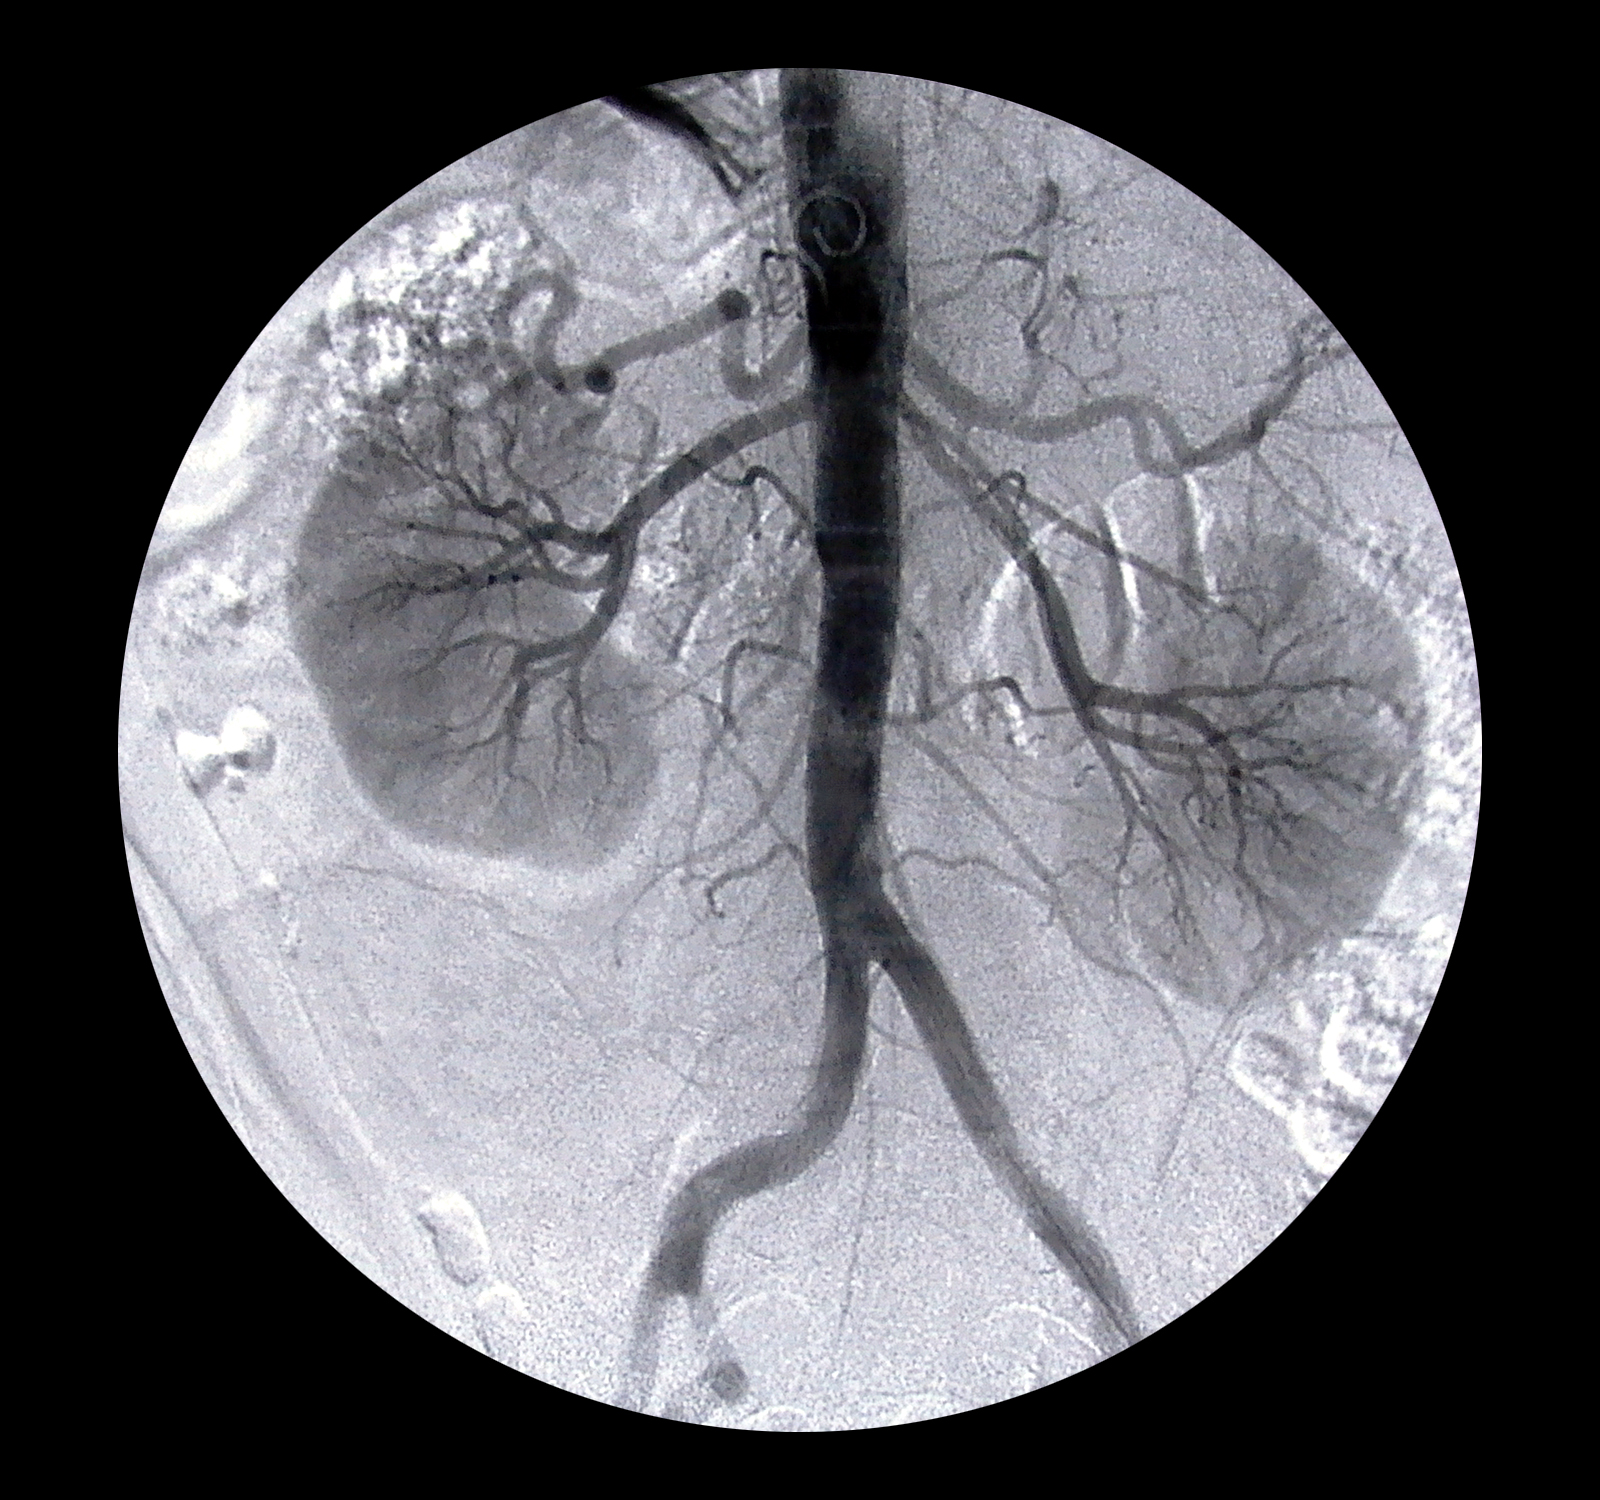

Para que se pueda dar un trasplante, suceden cuatro momentos diacrónicos. En primer lugar, la pérdida del riñón propio la cual suele ser progresiva. En segundo lugar, conseguir el órgano de un donante. En tercer lugar, la operación médica y para finalizar, la compatibilidad o éxito de la operación de trasplante.

Per tal que es pugui realitzar un trasplantament, esdevenen quatre moments diacrònics. En primer lloc, la pèrdua del ronyó propi la qual sol ser progressiva. En segon lloc, aconseguir l’òrgan d’un donant. En tercer lloc, l’operació mèdica i per finalitzar, la compatibilitat o èxit de l’operació de trasplantament.